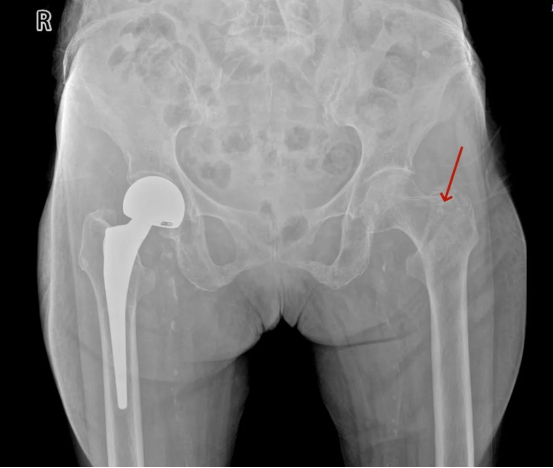

入院后床旁X线检查发现左股骨颈骨折

术后床旁X线检查